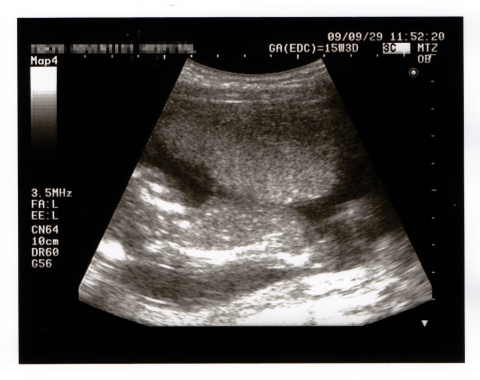

先日1ヶ月ぶりに定期健診に行って来ました。

検査の結果は特に問題なし!ただ、塩分を控えめにしてください、と言われてしまいました・・・。

赤ちゃんの姿も無事確認することが出来ました!

1ヶ月ぶりのお目見え

背骨がくっきり見えます。

私にはよく分からなかったのですが、Kenさんに言わせると、足をパタパタ元気に動かしていたそうです!

最近仕事で色々ストレスをかかえて悩んでいたのですが、赤ちゃんが元気だと知って、なんだか赤ちゃんに励まされた気がしました。